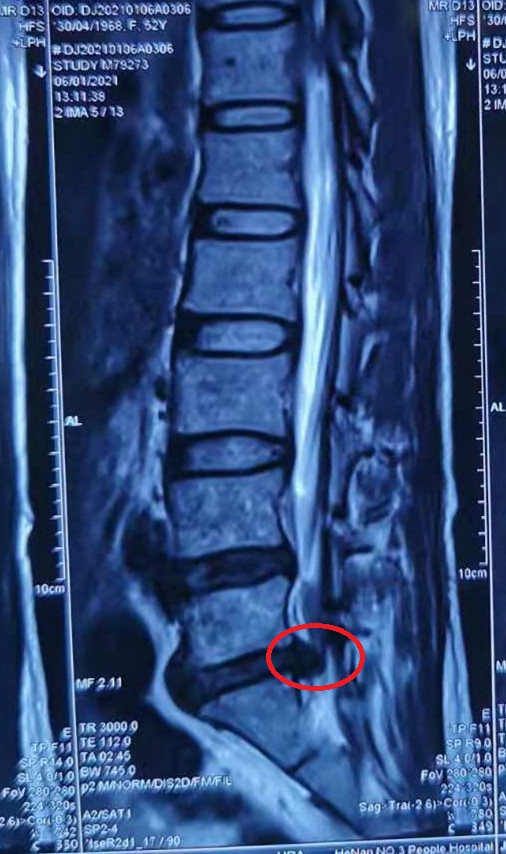

腰椎间盘突出症

患者,女,52岁,3个月前无明显诱因出现腰痛,并向右臀部及右小腿后侧放射,在当地医院诊断为腰椎间盘突出症,经过保守治疗,效果欠佳。近半个月来疼痛逐渐加重,多方打听遂来到我院椎间盘中心。

入院来,患者腰及右下肢疼痛难忍,只能膝胸位趴在床上,完善检查发现患者为腰5/骶1椎间盘突出(巨大型)。由于患者疼痛难忍,不能耐受常规局麻下内镜手术,为解决患者的痛苦,使患者尽快康复。椎间盘中心团队为患者制定了全麻下UBE技术椎板开窗椎间盘髓核摘除术。

术前 MRI 1